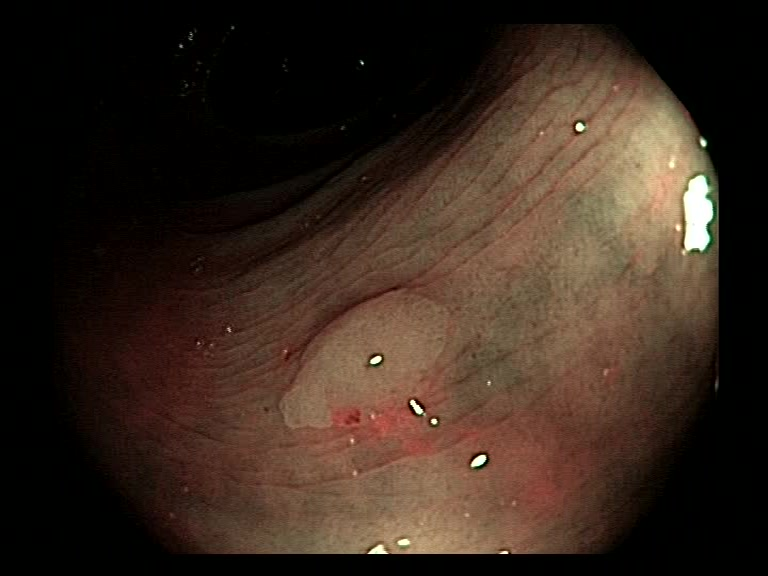

| Lesion | White Light Frame | NBI Frame | White Light Video | NBI Video | Camera Calibration |

| hyperplasic_01 |  |

|

WL.mp4 | NBI.mp4 | cam.xml |